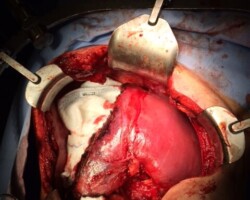

Resection of large retroperitoneal sarcoma including right and transverse colectomy and right hepatectomy